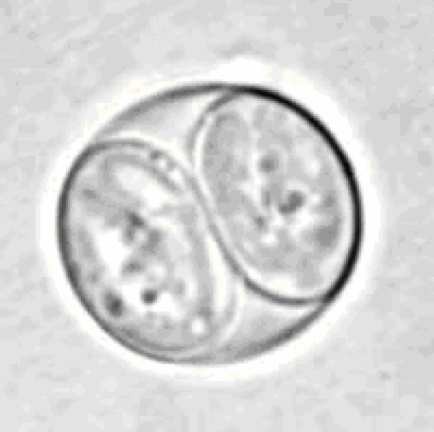

Цисты и ооцисты простейших

Цисты и ооцисты простейших 109 фотографий